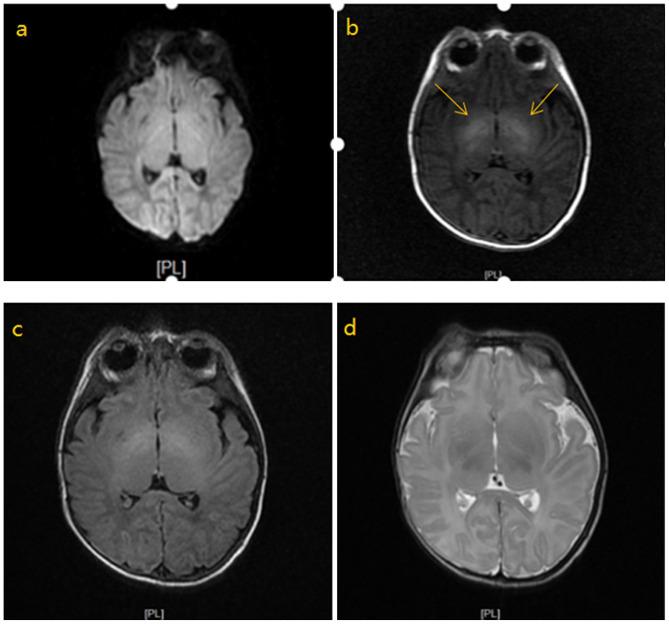

The present study aimed to explore the diagnostic value of the combination of cranial magnetic resonance imaging (MRI), serum homocysteine (HCY) and procalcitonin (PCT) for hyperbilirubinemia complicated with brain injury in neonates. One hundred and forty-nine children with hyperbilirubinemia admitted to Shandong Medical Imaging Research Institute from January 2014 to April 2016 were collected as research subjects, and were divided into a brain injury group (n=67) and a non-brain injury group (n=82) according to whether children suffered from brain injury. PCT levels were detected by electrochemiluminescence (ECL), and HCY levels by enzymatic cycling assay (ECA). The combination of cranial MRI, HCY and PCT was used to diagnose hyperbilirubinemia complicated with brain injury in neonates. The concentrations of HCY and PCT in the brain injury group were significantly higher than those in the non-brain injury group (P<0.001). According to the MRI examination results, the patients were divided into an MRI normal group and an MRI abnormal group. In the brain injury group, the serum HCY and PCT levels of the MRI abnormal group were significantly higher than those of the MRI normal group, with a statistically significant difference (P<0.05). In the non-brain injury group, the serum HCY and PCT levels of the MRI abnormal group were significantly higher than those of the MRI normal group, with a statistically significant difference (P<0.05). The sensitivity of the combined detection was significantly higher than that of single detection (P<0.05); the specificity was significantly higher than that of HCY detection (P<0.05), and the accuracy was significantly higher than that of MRI and HCY single detection (P<0.05). In conclusion, the combination of cranial MRI, HCY and PCT, which has a high diagnostic value for hyperbilirubinemia complicated with brain injury in neonates, is conducive to the early diagnosis and timely treatment of the disease and the reduction of sequelae.